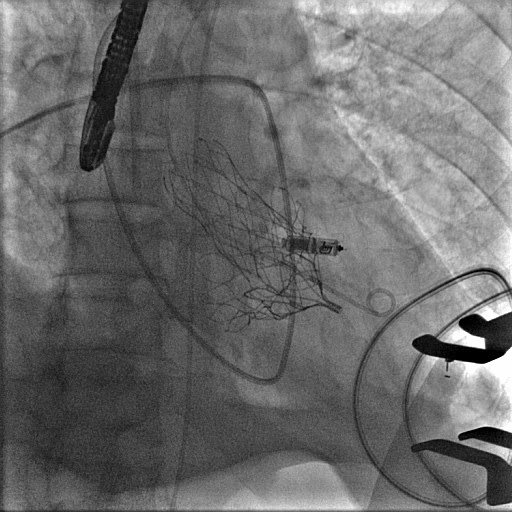

La pose de la bioprothèse Tendyne™ est une procédure sophistiquée et moins invasive que la chirurgie classique. En effet, cette procédure se déroule sans arrêt du cœur, ni recours à la circulation extracorporelle, ce qui diminue considérablement les risques opératoires et les complications postopératoires. Cette technique se réalise par une insertion d’un cathéter à travers une petite incision (environ 3 cm) réalisée au niveau du thorax, entre les côtes. La prothèse est guidée jusqu’au cœur via le ventricule gauche, où elle est déployée avec une précision millimétrée pour remplacer la valve mitrale défectueuse.

L’intervention, réalisée sous anesthésie générale, est guidée en temps réel par Dr Mathieu, cardiologue échographiste avec des techniques d’imagerie avancée : échographie transœsophagienne 3D et fluoroscopie. Cela permet à l’équipe chirurgicale de visualiser et d’assurer le guidage à chaque étape de l’opération. L'introduction du cathéter permet de positionner et d'ancrer la prothèse directement dans la valve native.